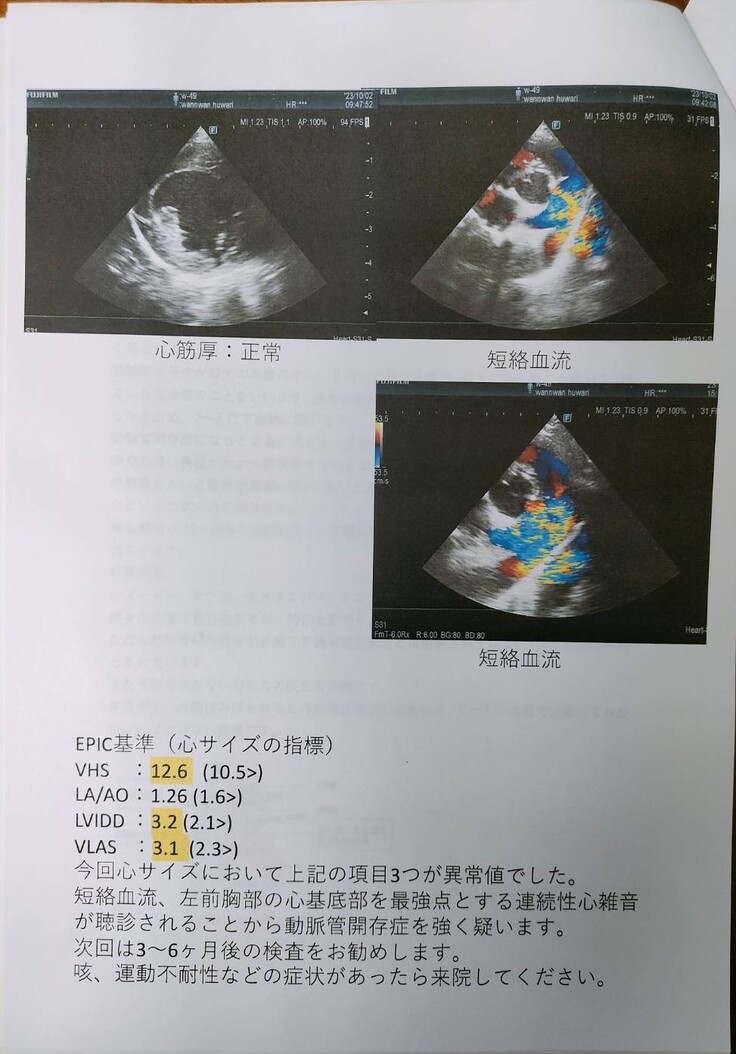

Y動物病院にて診療すると、動脈管開存症(PDA)であることがわかり、手術のできるR動物病院を紹介していただきました。

すぐ、Y動物病院で診てもらったところ、動脈管開存症(PDA)と診断され、手術のできるR動物病院を紹介していただきました。

メスの4歳チワワです。心臓の動脈管開存症(PDA)と診断され、一刻も早く手術をしたほうが良いと先生からのお話しをいただきまして、緊急で手術をしました。

チワワのふわりちゃんは心臓の動脈管開存症との診断でした。